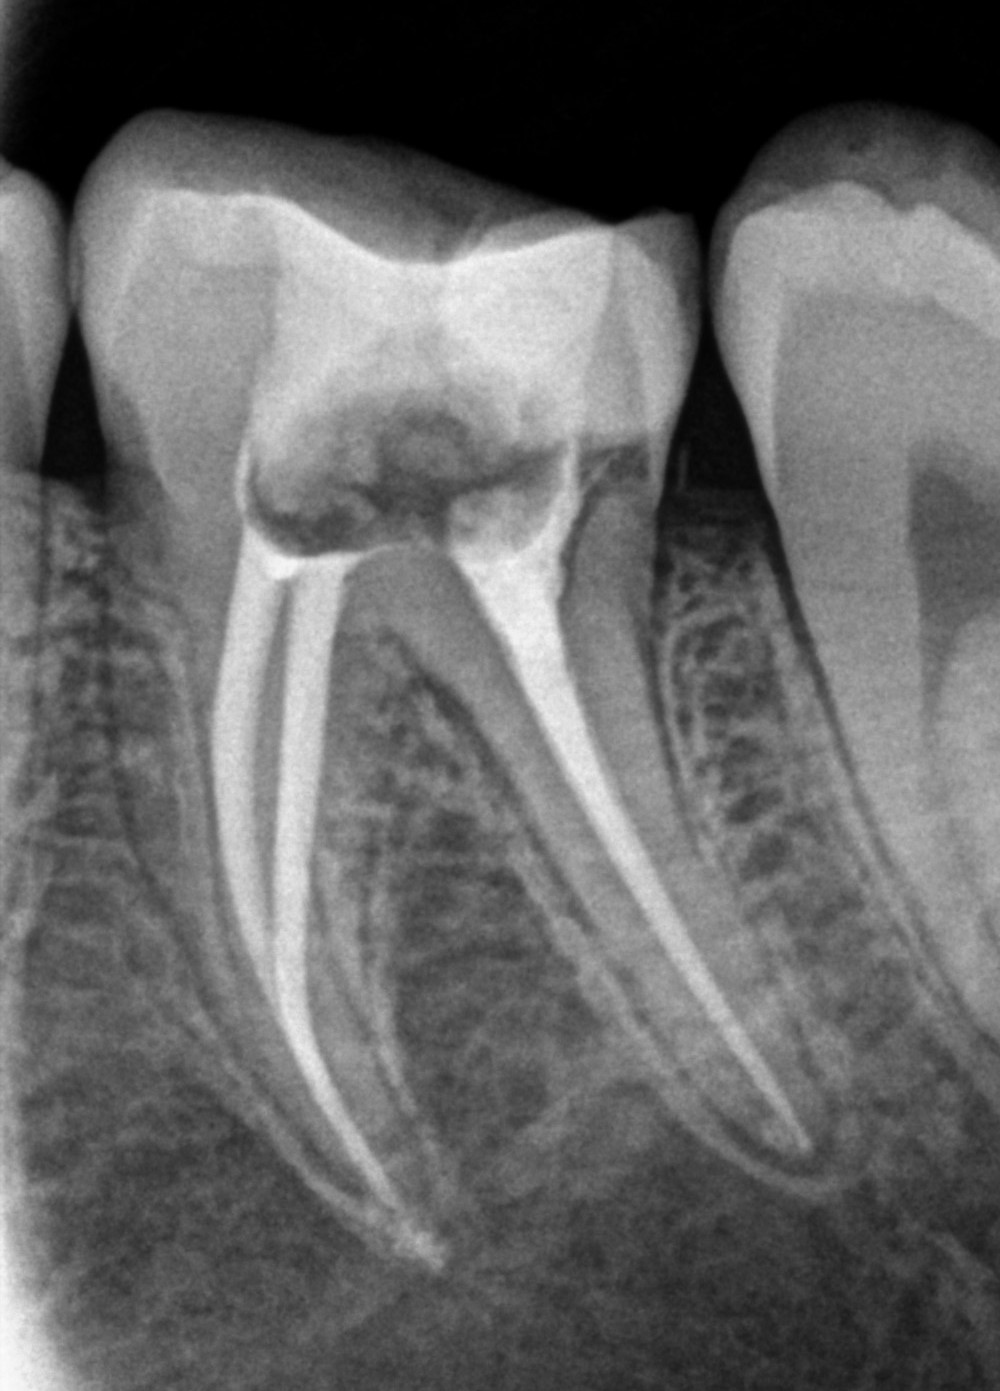

See My Work

Cases